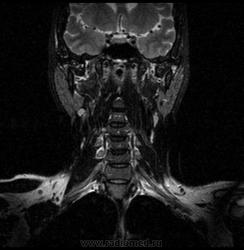

06.06.2011 МРТ - головы и шеи.

Пацентка 36 лет, с жалобами на припухлось в околоушной области справа.

В глубокой доле  правой околоушной железы  на фоне неизмененной паренхимы зона  гетерогенного по Т2, гипоинтенсивного по Т1  с единичными гиперинтенсивными включениями.При контрастировании- накопление контраста диффузное неоднородное и по периферии.Рискну предположить злокачественное образование ( аденокарцинома) с низкой степенью злокачественности( есть капсула, экспансивный рост).Сильно не расстреливайте.

Проблема в том, что перед челюстно-лицевым хирургом стоит распространенность любого объемного процесса, в данном случае все упирается в возмможную травму лицевого нерва и конечно же с дальнейшим его парезом, а ведь женщина  еще молодая. Образование имеет тонкостенную оболочку, по структуре неоднородно, с наличием кальцината, при этом МР-сигнал от окружающих анатомических структур(как костных так и мышечных) не изменен, т.е. об инфильтративном росте речи не идет, в какой то степени доброкачественное. В конкретном случае лицевой нерв с ретромандибулярной веной просто несколько оттеснен.

По гистологии аденома околоушной слюнной железы, но после удаления пока сохраняется парез лицевой мускулатуры, возможно временный.